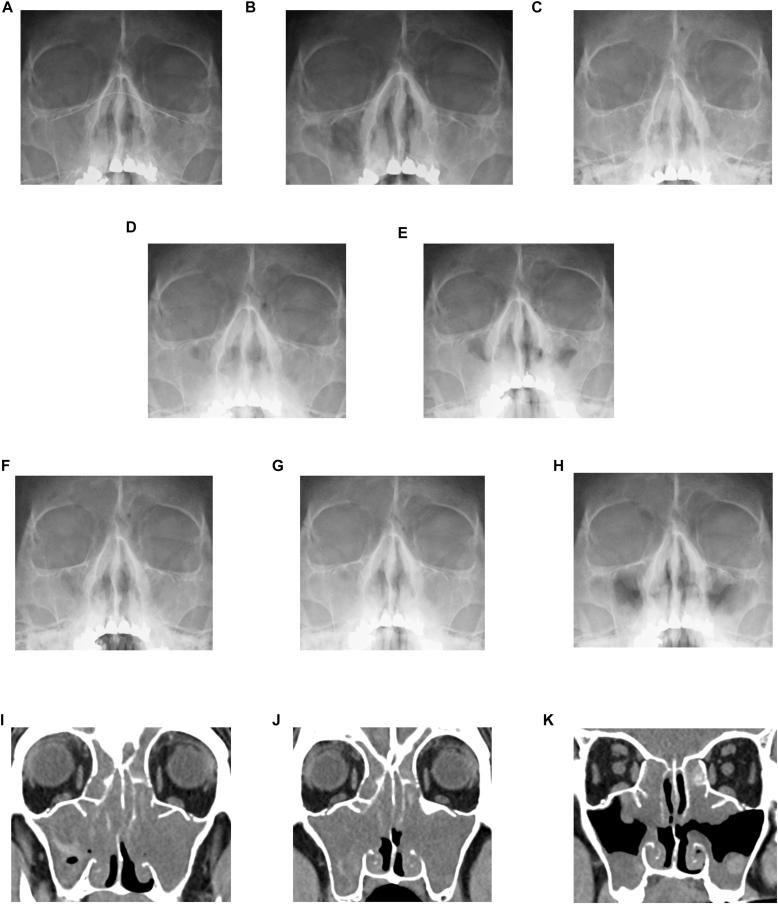

Tezepelumab, a mAb targeting thymic stromal lymphopoietin (TSLP), reduces exacerbations in severe asthma. Four cases in which patients with severe asthma and chronic rhinosinusitis with nasal polyps showed improvements in both conditions after receiving tezepelumab treatment are presented.

tezepelumab是一种靶向胸腺基质淋巴细胞生成素(TSLP)的单克隆抗体,可减少重度哮喘的发作。本文介绍了4例重度哮喘合并慢性鼻-鼻窦炎伴鼻息肉患者在接受tezepelumab治疗后,两种疾病均得到改善的病例。